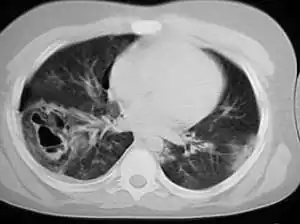

| A chest CT scan revealing pulmonary contusions, pneumothorax, and pseudocysts | |

Pseudocysts are like cysts, but lack epithelial or endothelial cells. Initial management consists of general supportive care. Symptoms and complications caused by pseudocysts require surgery. Computed tomography (CT) scans are used for initial imaging of cysts, and endoscopic ultrasounds are used in differentiating between cysts and pseudocysts. Endoscopic drainage is a popular and effective method of treating pseudocysts.